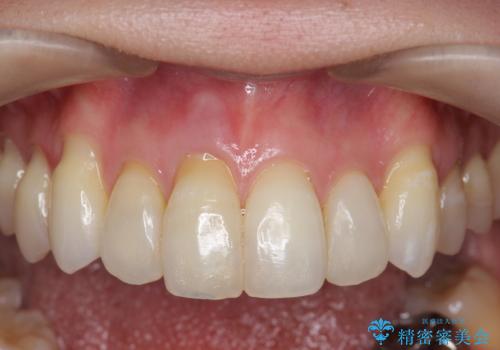

吸収し喪失した前歯、ブリッジによる審美性の回復

- 前医に前歯の吸収による抜歯の必要性を伝えられ、前歯の審美的な改善・治療を求めて来院されました。